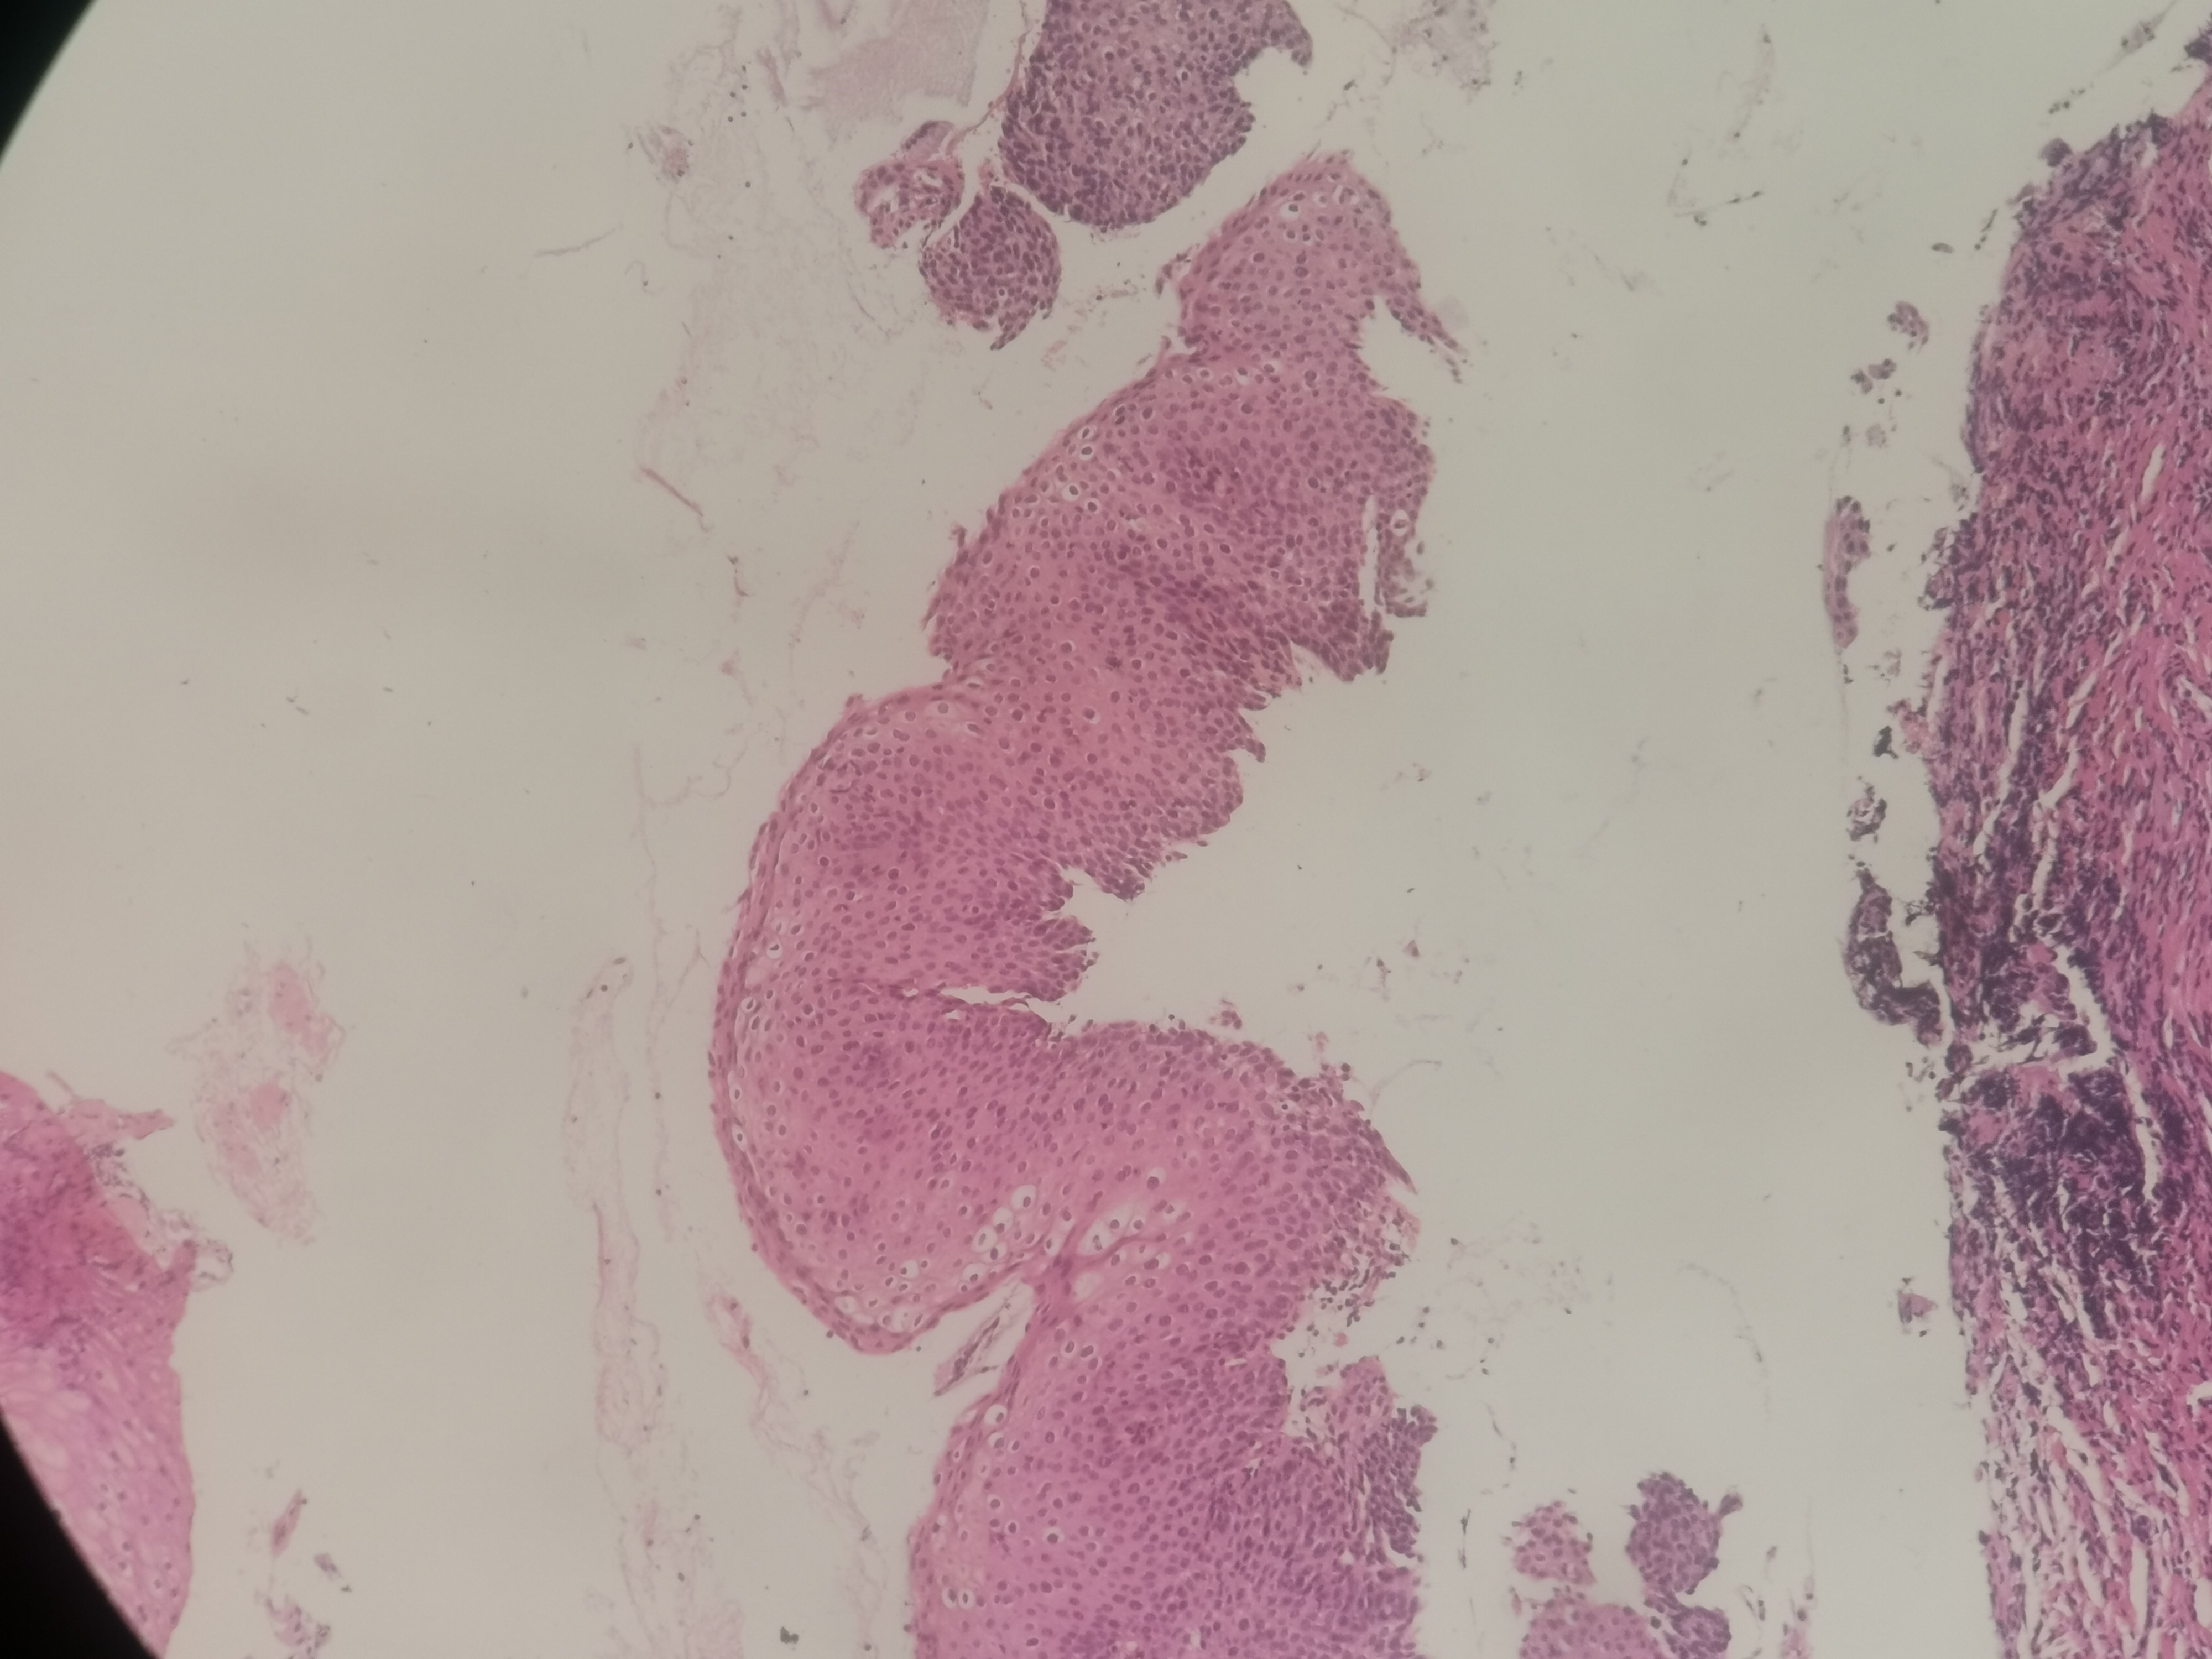

急!请老师帮忙看看,12点够CINii吗,还是报CINI~II

性别

女

年龄

59岁

临床诊断

HPV感染

一般病史

HPV16(+)

标本名称

宫颈活检组织

大体所见

3点:0.8x0.4x0.3厘米1块。6点0.7x0.6x0.3厘米1块。9点0.6x0.6x0.4厘米1块。12点0.8x0.5x0.3厘米,0.6x0.6x0.4厘米2块。

图1~16为12点2块组织,图17为9点组织,图18,为6点组织,图19为3点组织。

倾向低级别,标记看看